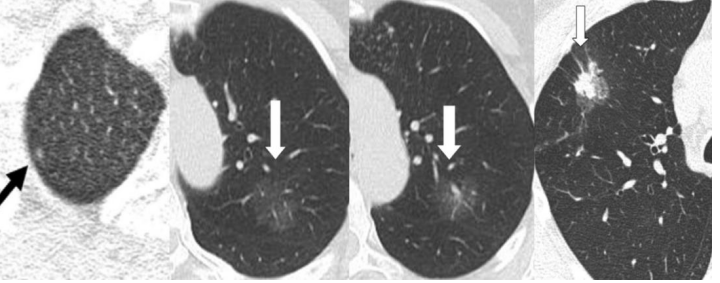

肺癌的发展是渐进性的,典型的肺癌是有自身的演化逻辑的:先慢后快。首先是不典型腺瘤样增生(AAH)——然后是原位癌(AIS)——再接着是微浸润癌(MIA)——最后是浸润性癌。从AAH发展到MIA可能需要10年时间,这期间肿瘤的生长是极其缓慢的,理论上是不会有转移的。而AIS或者MIA的倍增时间(请注意,这里指的倍增是体积倍增,要知道体积倍增是直径的倍增8倍)一般要超过2年。

图六 由左到右依次为非典型腺瘤样增生,原位腺癌,微浸润癌,贴壁生长为主的腺癌